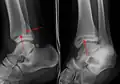

Fracture of both sides of the ankle with dislocation as seen on anteroposterior X-ray. (1) fibula, (2) tibia, (arrow) medial malleolus, (arrowhead) lateral malleolus | |